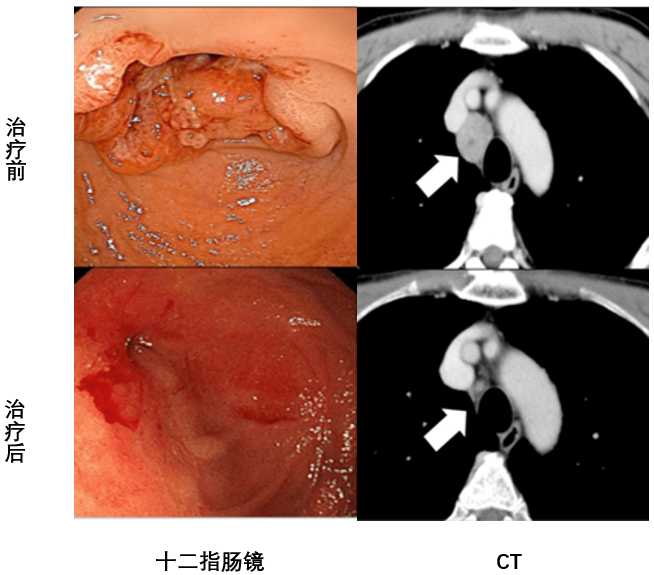

在绝境之下,患者于2021年7月接受新抗原负载的DC疫苗联合DC-CTL细胞治疗,每周一次,连续八周。治疗后腹水消失,症状显著改善,无不良反应。患者后续每6个月接受增强/维持治疗,已保持54个月无复发。